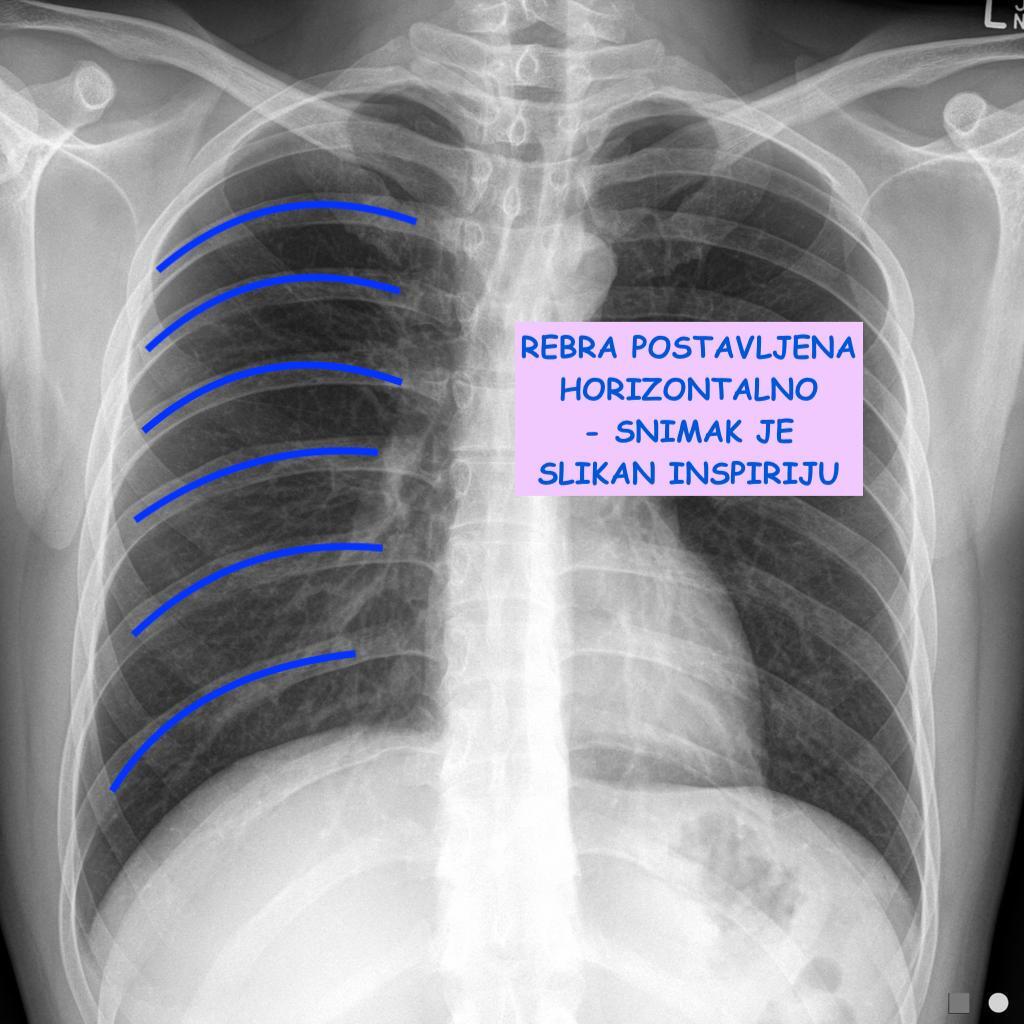

⁃ Faza respiracije (kao što smo već rekli, horizontalno postavljena rebra su potvrda da je snimak napravljen u inspiriju).